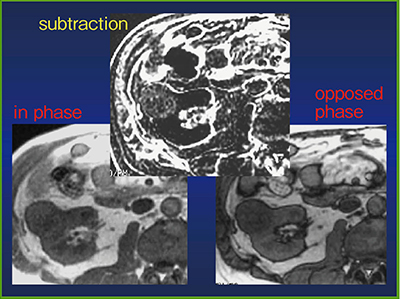

また,腎腫瘤のタイプは血流でも鑑別できるが,MRIのT2強調画像における信号の違いも役に立つ(図2)。特に,淡明細胞癌はin phaseに比べてopposed phaseでは低信号となることがある(図3)。

図3 MRIによる細胞内脂肪の描出

淡明細胞癌は細胞に含む脂質をMRIで確認できることが多い。

単純CTにおいて,CT値が10HU以下なら,98%は副腎腺腫である。CT値が10〜30HUの場合は確実には診断できないため,CTヒストグラムや化学シフトMRIで細胞内の脂肪を確認する。

また,化学シフトMRIのopposed phaseで信号が下がれば副腎腺腫,下がらなければ転移と診断できる(図5)。CT値が30HU以上の場合は,造影CTを施行する。

図5 化学シフトMRIでの副腎腺腫と副腎転移の鑑別